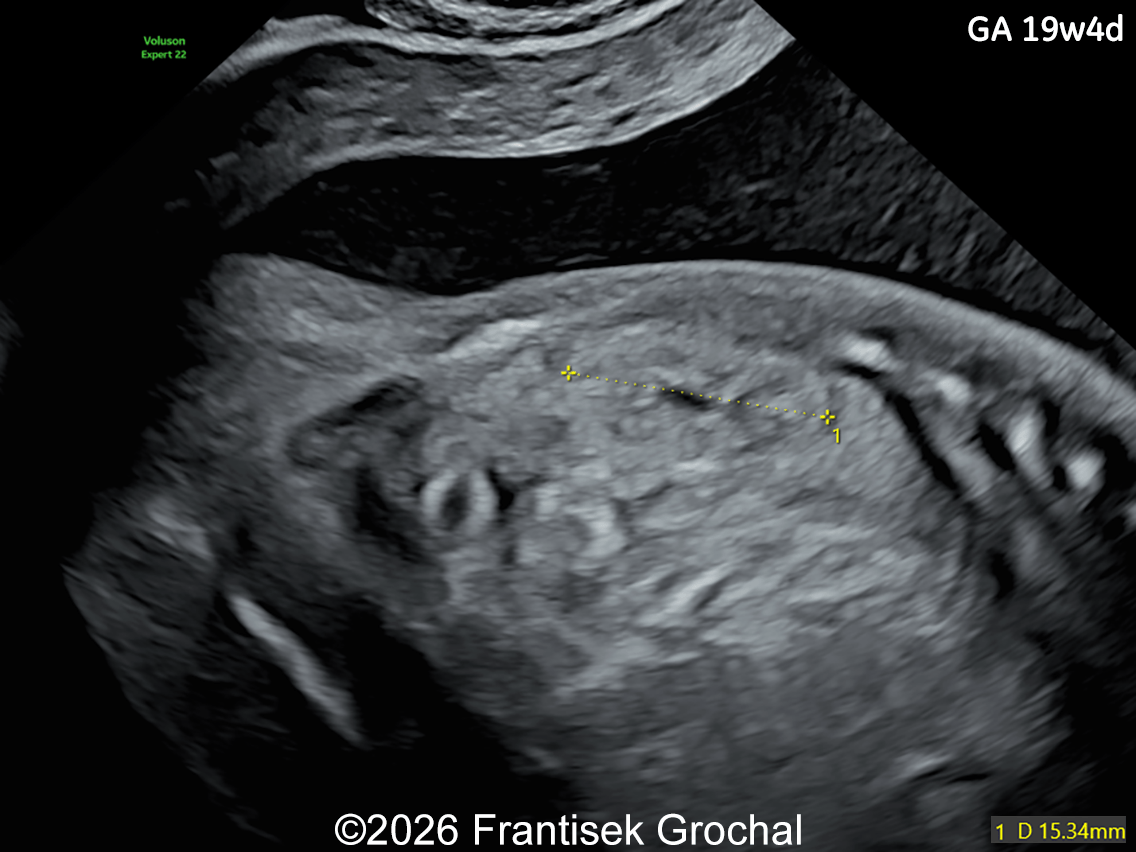

Image 1

Ultrasound examination at 14 weeks demonstrated marked nuchal edema, nasal bone hypoplasia, and a suspected ventricular septal defect.

• Marked nuchal edema

• Prefrontal edema

• Nasal bone hypoplasia

• Micrognathia

19+4 weeks of gestation; sagittal view of the fetal head demonstrating prefrontal edema, nasal bone hypoplasia, retrognathia, and a short corpus callosum.

Image 1 19+4 weeks of gestation; sagittal view of the fetal head demonstrating prefrontal edema, nasal bone hypoplasia, retrognathia, and a short corpus callosum.